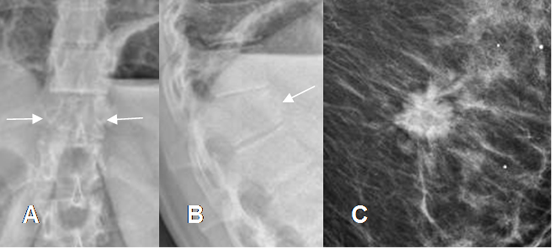

Fig 50 A. Tumor metastásico.

A: Rx AP y B: Rx lateral. Pérdida en la nitidez de los contornos de D12 y leve disminución de altura, en su parte anterior.

C: Mamografía: Lesión espiculada y densa, por neoplasia de mama.